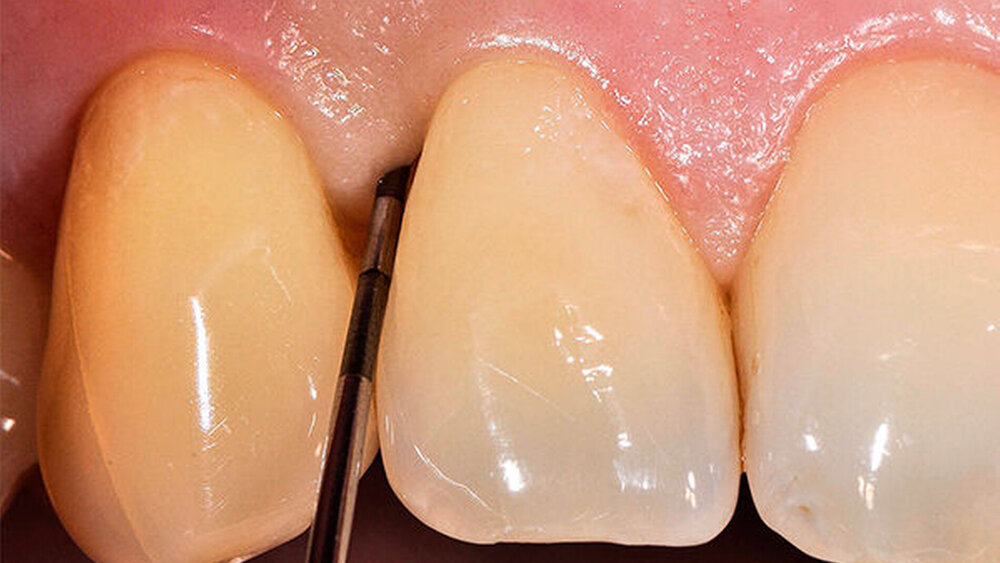

Als unterstützende Therapie zur mechanischen Reinigung wurde ein PerioChip eingesetzt, mit dem Ziel einer weiteren Reduktion der Sondierungstiefe. Weitere vier Monate später wurde die Sondierungstiefe auf 4 mm reduziert, ohne klinische Entzündungszeichen, d. h. Bluten auf Sondierung (Abb. 3).